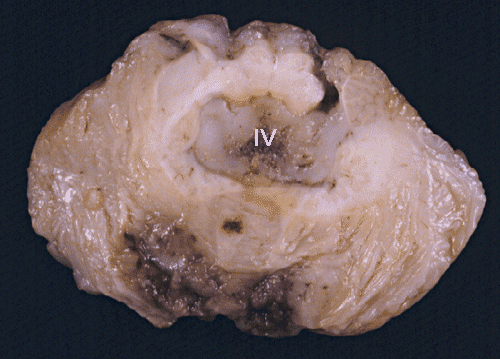

- Panel A: Medulloblastoma arise with the

posterior fossa. In this particular case, the tumor filled and expanded the

4th ventricle (IV).